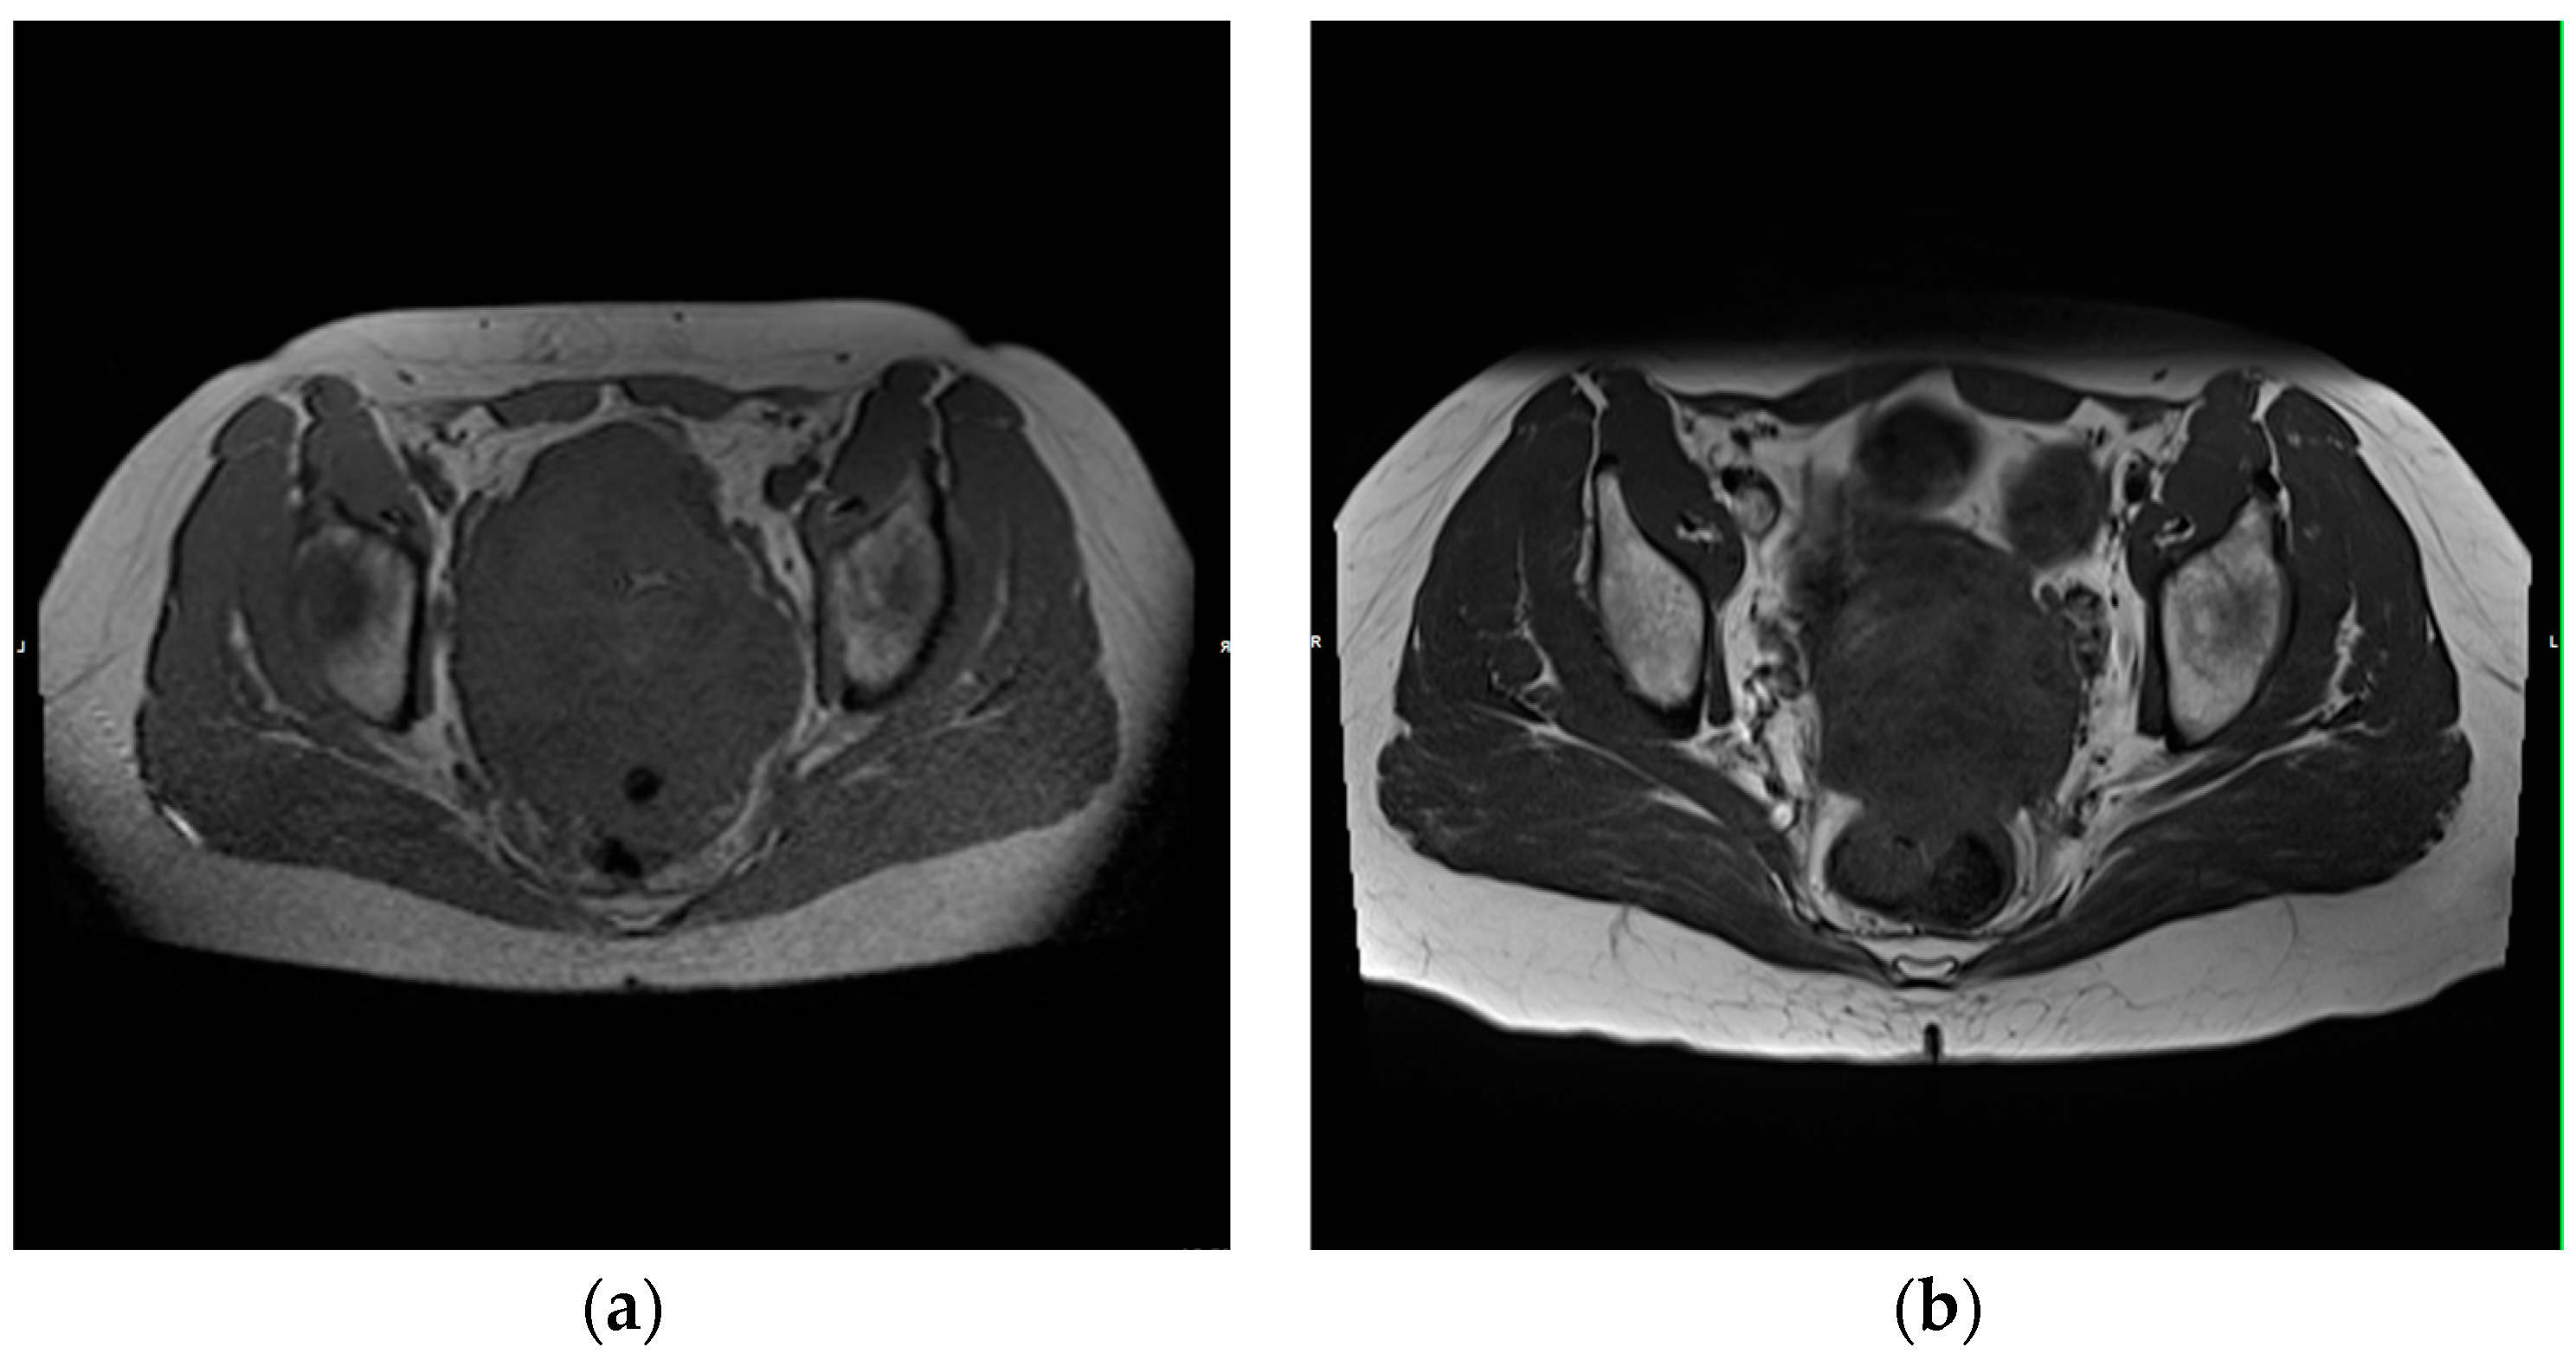

Figure 3. A 47-year-old patient diagnosed with ovarian carcinoma underwent eight TACP procedures. Following the completion of the treatment cycle, the measurements demonstrated a reduction of 34% in the longest diameter. Consequently, the patient exhibited a partial response. (a) Transverse T1-weighted image of the pelvis that depicts the tumor prior to the initiation of therapy; (b) Transverse T1-weighted image of the pelvis that shows the tumor following the completion of eight TACP procedures, which resulted in a significant reduction in the longest diameter.